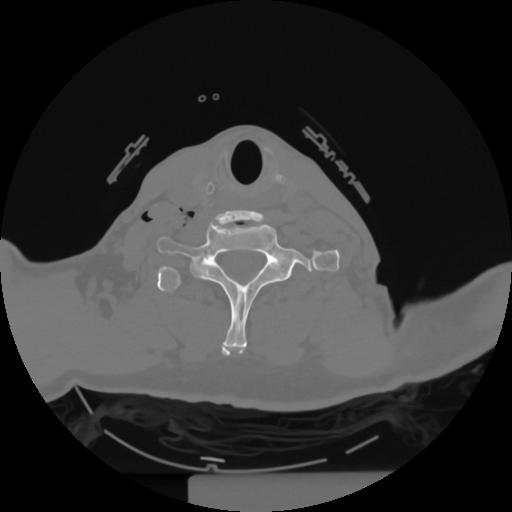

12 P.BLANDAS,,Vol,0.5,P.BLANDAS,,